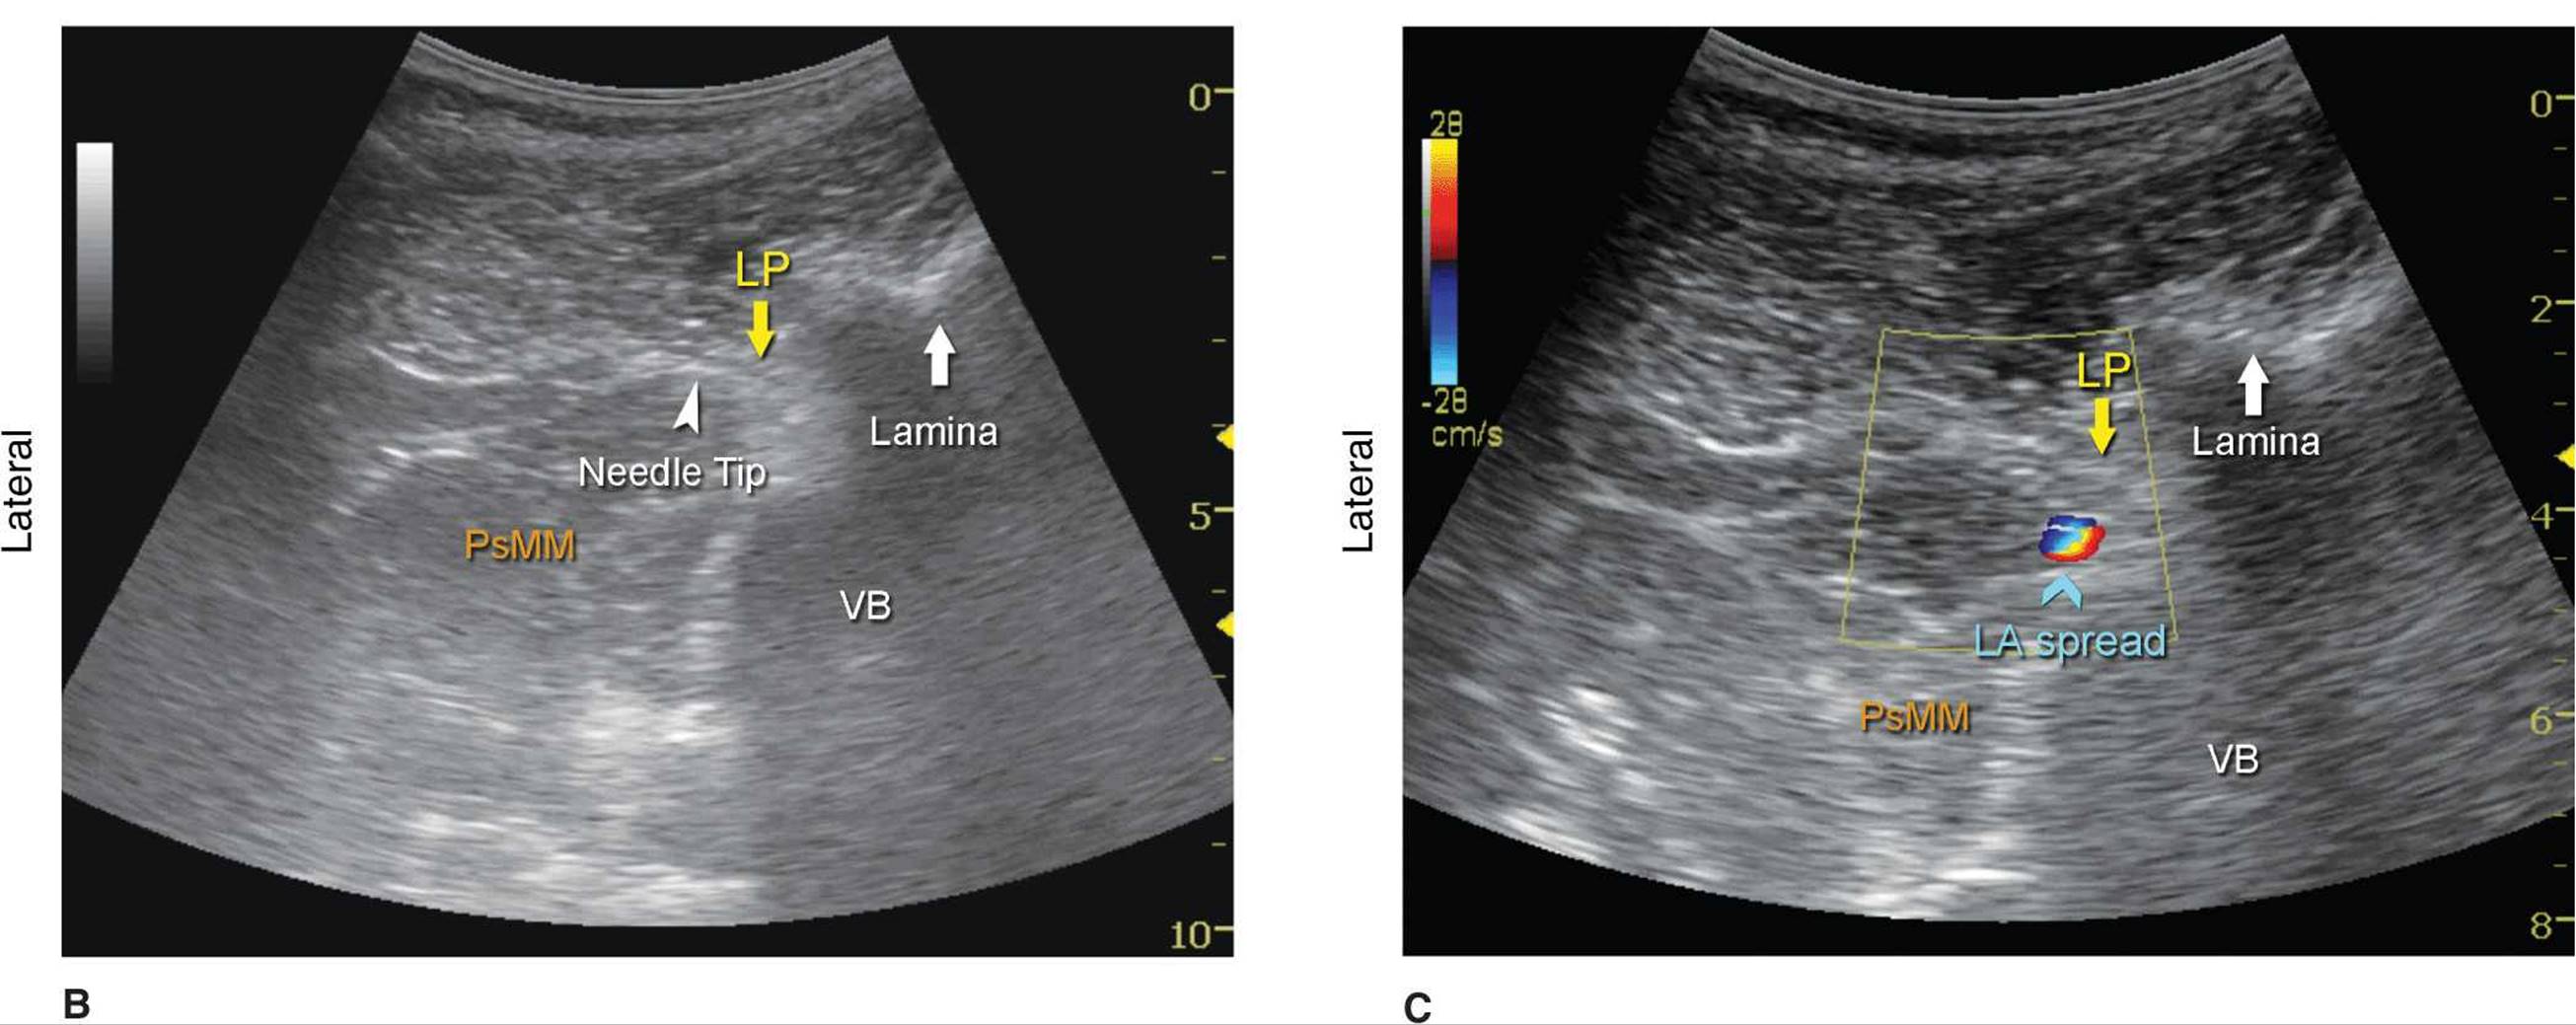

Kirchmair and colleagues were among the first to describe the sonoanatomy of relevance for LPB.3 They reported the ability to accurately guide a needle to the posterior part of the psoas muscle, where the roots of the lumbar plexus are located, using ultrasound guidance in cadavers.4,5 Since, significant advances in ultrasound technology have taken place, allowing for much improved image quality, which have allowed Karmakar and colleagues to devise an alternative approach to the lumbar plexus using ultrasonographic identification of the transverse processes as the guide.6 With this scanning technique, the transducer is positioned 4 to 5 cm lateral to the lumbar spinous process at the L3-L4 level and directed slightly medially to assume a transverse oblique orientation (Figure 46-4). This approach allows imaging of the lumbar paravertebral region with the erector spinae muscle, transverse process, the psoas major muscle, quadrates lumborum, and the anterolateral surface of the vertebral body (Figure 46-5A, B, and C). In the transverse oblique view, the inferior vena cava (IVC), on the right-sided scan, or the aorta, on the left-sided scan, also can be seen and provide additional information on the location of the psoas muscle, which is positioned superficial to these vessels. In this view, the psoas muscle appears slightly hypoechoic with multiple hyperechogenic striations within. The lower pole of the kidney can often be seen, when scanning at the L2-L4 level, as an oval structure that ascends and descends with respirations (Figure 46-6). The key to obtaining adequate images of the psoas muscle and lumbar plexus with the transverse oblique scan is to insonate between two adjacent transverse processes. This scanning method avoids acoustic shadow of the transverse processes, which obscures the underlying psoas muscle and the intervertebral foramen (angle between the transverse process and vertebral body) and allows visualization of the articular process of the facet joint (APFJ) as well. Because the intervertebral foramen is located at the angle between the APFJ and vertebral body, lumbar nerve roots often can be depicted.

FIGURE 46-5. (A) Ultrasound anatomy of the lumbar paravertebral space using transverse oblique view. SP, spinal process; ESM, erectors spinae muscle; QLM, quadratus lumborum muscle; PsMM, psoas major muscle; VB, vertebral body. The lumbar plexus root is seen just below the lamina as it exits the interlaminar space and enters into the posterior medial aspect of the PsMM. (B) Needle path in ultrasound-guided lumbar plexus block using transverse oblique view. LP, lumbar plexus; PsMM, psoas major muscle; VB, vertebral body. (C) Spread of the local anesthetic solution with lumbar plexus block injection. Due to the deep location of the plexus, spread of the local anesthetic may not always be well seen. Color Doppler imaging can be used to help determine the location of the injectate.

A paramedial scan also can be used with an in-plane needle approach. In this technique, an insulated needle is inserted in-plane from the caudal end (Figure 46-4) of the transducer while maintaining the view of the transverse processes. Again, the goal is to pass the needle and inject local anesthetic with a real-time visualization of the needle path and injection into the posterior part of the psoas muscle (Figure 46-5).